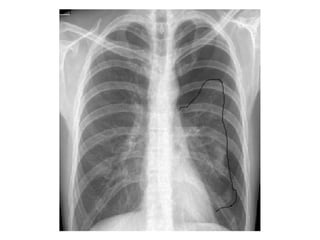

Hemotórax

Quando suspeitar? na presença de:

• Taquipnéia;

• Dor torácica;

• Respiração superficial;

• MV ausente ou diminuído do lado afetado;

• 90% dos casos o tratamento é eficiente

apenas com drenagem.

• 10% é necessário intervenção cirúrgica,

toracotomia ou laparotomia exploradora.

• Pode apresentar -se normotenso ou

hipertenso.

• Quando hipertenso está associado a

pneumotórax.

• Macicez à percussão do hemitórax afetado;

• Sinais clínicos de choque (cada espaço pleural

pode reter até 2500 a 3000 ml de sangue,no

adulto);

• Confusão mental e ansiedade, dependendo da

magnitude do comprometimento respiratório e

cardiovascular;

• Pensar na associação com pneumotórax,

especialmente nos traumas penetrantes.

O sangue coletado na cavidade pleural tem

4 origens:

• Parênquima pulmonar (90% dos casos);

• Vasos sistêmicos (intercostais,

mamários);

• Lesões de mediastino (coração, vasos da

base);

• Ferimentos toraco-abdominais

Classificação

• Pequeno: 300 a 350 ml de sangue

drenado

• Médio: 350 a 1500 ml de sangue drenado

• Grande: maior que 1500 ml

• Tratamento

• Drenagem torácica